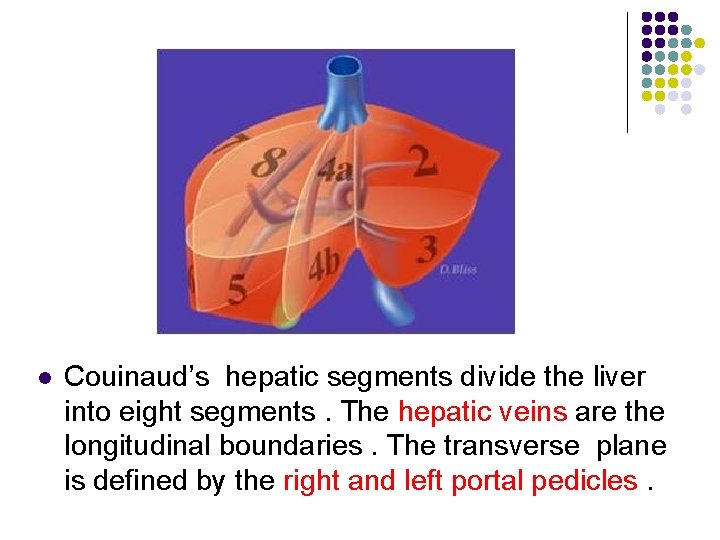

Hepatic Nomenclature l Couinaud’s system of hepatic nomenclature provides the anatomic basis for hepatic surgical resection. By using this system , the radiologist may be able to precisely isolate the location of a lesion for the surgical team

l Couinaud’s hepatic segments divide the liver into eight segments. The hepatic veins are the longitudinal boundaries. The transverse plane is defined by the right and left portal pedicles.